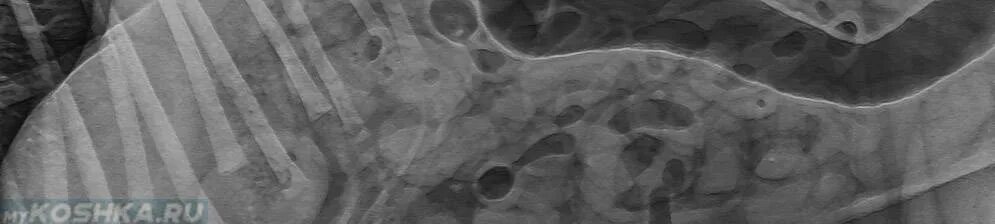

Лимфома у собак симптомы